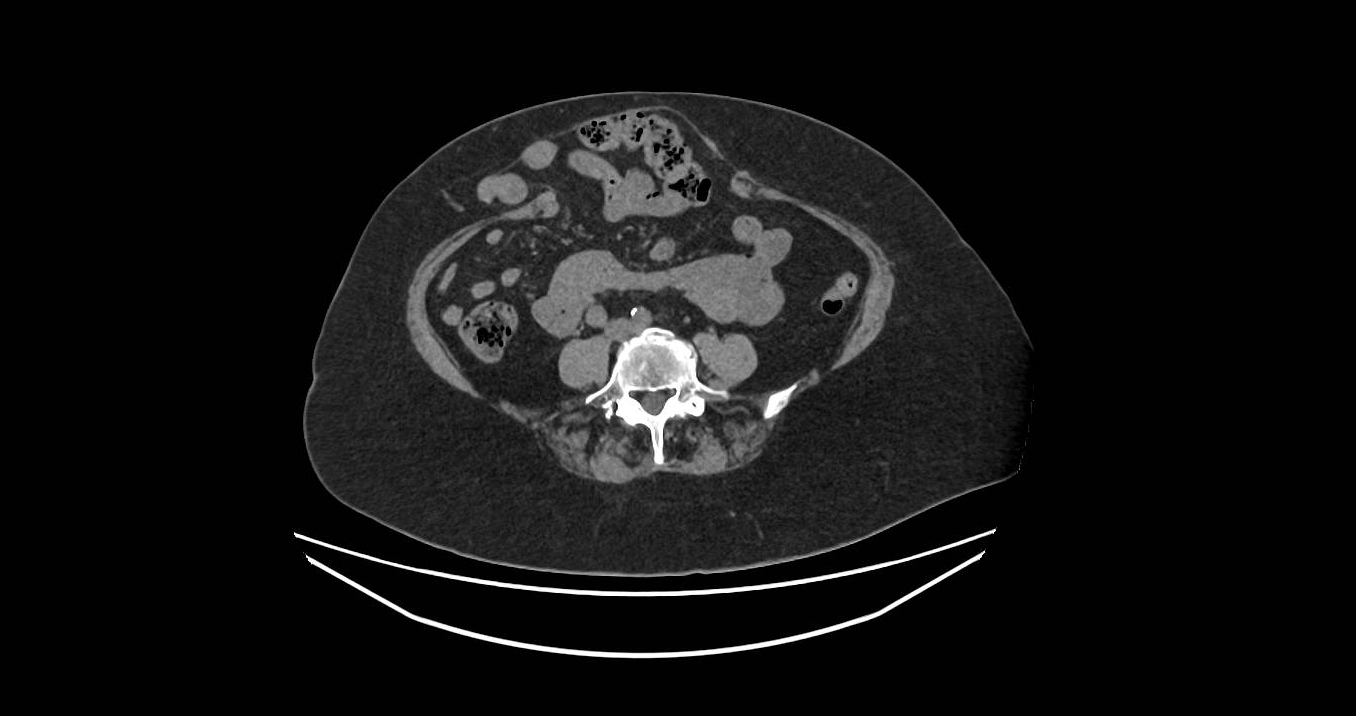

The decision about open or keyhole surgery and the need for abdominal wall reconstruction is based on the site and size of the hernia and the defect, other associated defects in proximity to the main hernia, the extent of separation of the muscles and the quality of the muscles. Proper planning, including the use of the CT scan, leads to the development of an approach that is individualised to each person.